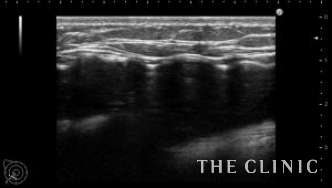

本日紹介する方は左胸の痛みで来院、見た目や触診では問題ありませんでしたが、エコー検査で左胸のバッグが破損していました。エコー所見です。右は軽度のカプセル拘縮を認めますが、左は破損してカプセル内にシリコンが漏れていました。腋の下からバッグを取り出しましたが、左のカプセル内にはシリコンが漏れていました。

バッグの破損があると術後にカプセル内にリンパ液が貯留する場合がありますが、

1週間後のエコーではリンパ液の貯留もなく問題ありませんでした。バッグの破損は自覚症状がない場合も多いので、定期的にエコー検査をするべきだと思います。